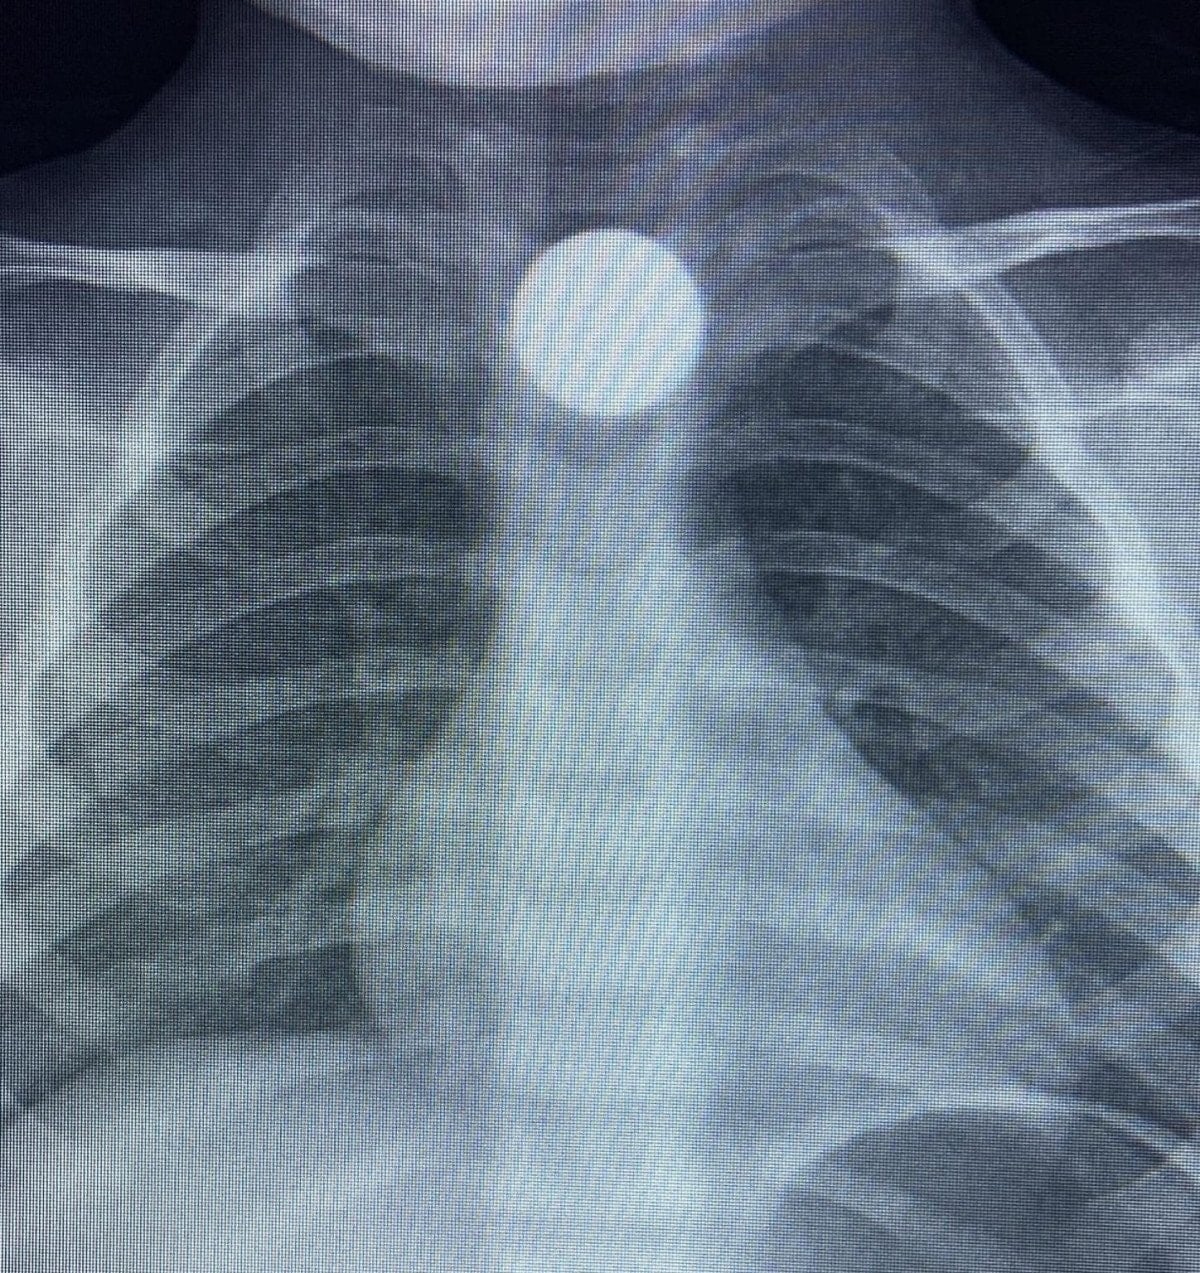

Çocuğun parayı yuttuğunu fark eden ailesi, Bilal K.’yi vakit kaybetmeden özel araçla İnegöl Devlet Hastanesi’ne götürdü. Hastanede yapılan muayene ve görüntüleme işlemlerinde, madeni paranın çocuğun yemek borusunda takılı kaldığı tespit edildi.

İlk müdahalesi İnegöl Devlet Hastanesi’nde yapılan Bilal K., ileri tetkik ve tedavi amacıyla ambulansla Bursa Yüksek İhtisas Eğitim ve Araştırma Hastanesi’ne sevk edildi.